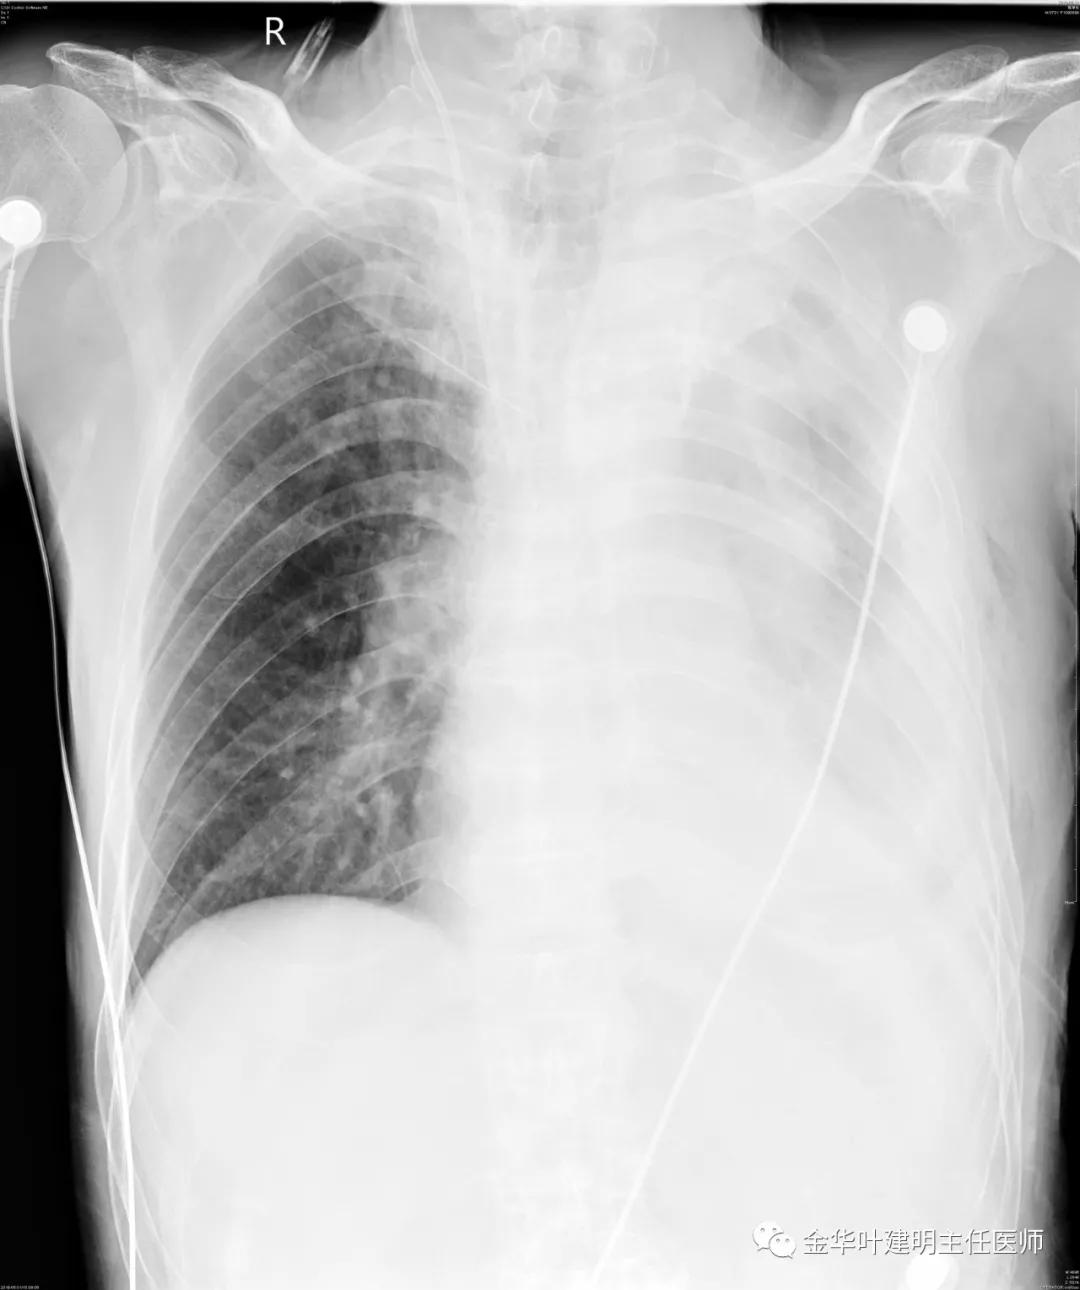

5.31下午7时,从早上开始算胸引700毫升,共900毫升;予以查床边,胸片,结果如下:

考虑左侧大量胸腔积液,遂进一步胸部CT检查: